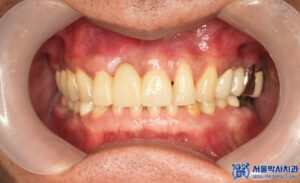

위 환자분은 위 앞니가 심하게 흔들리면서

씹을 때마다 불편감을 느낀다고 하셨는데요.

진단 결과, 문제의 치아는 위 앞니 중에서도

정중앙에 위치한 오른쪽 큰 앞니로,

치아 상태도 많이 나빠져 있었고

만성 치주염으로 인해 치근 끝에

염증이 크게 퍼져 흔들림이 있는 상태였습니다.